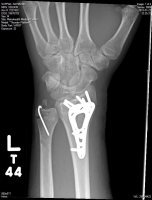

In all seriousness Ray I hope you heal up quickly. I dont know how old these images are, but man that had to really hurt like a SOB!

about 2 weeks :devil: it wasnt too bad, i manned up and didnt cry. but thank you very much!

Yeah thats a tough one... You probably just thought you twisted it.... did something similar to my wrist and thought I sprained it... a couple of years later I was at the doctors for an insurance physical and he had asked when I had broken my wrist...... "What you mean broken wrist?" An Xray he took revealed a broken radious...:shocked: :lol: :noidea: